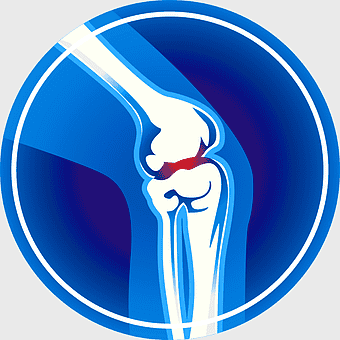

knee pain symptoms, joint pain illustration, arthritis blue icon, osteoarthritis medical diagram, human body joint health, bone condition visual, joint discomfort -